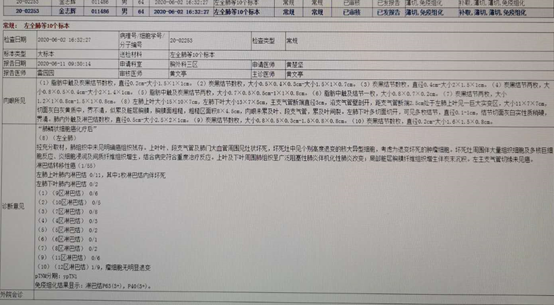

微创单孔胸腔镜左全肺切除+系统性淋巴结清扫+系统性淋巴结清扫,术后恢复好,1周出院。

术后病理诊断结果,N1淋巴结均可见转移,术后病理分期为中期。

经验总结,此例患者发现已经为局部晚期,肿瘤已经侵犯周围血管及主支气管,经过两个周期的免疫+化疗两个周期后,病灶明显缩小较,经手术治疗后达到完整切除,术后病理可见局部淋巴结转移,继续给与免疫+化疗两个周期。